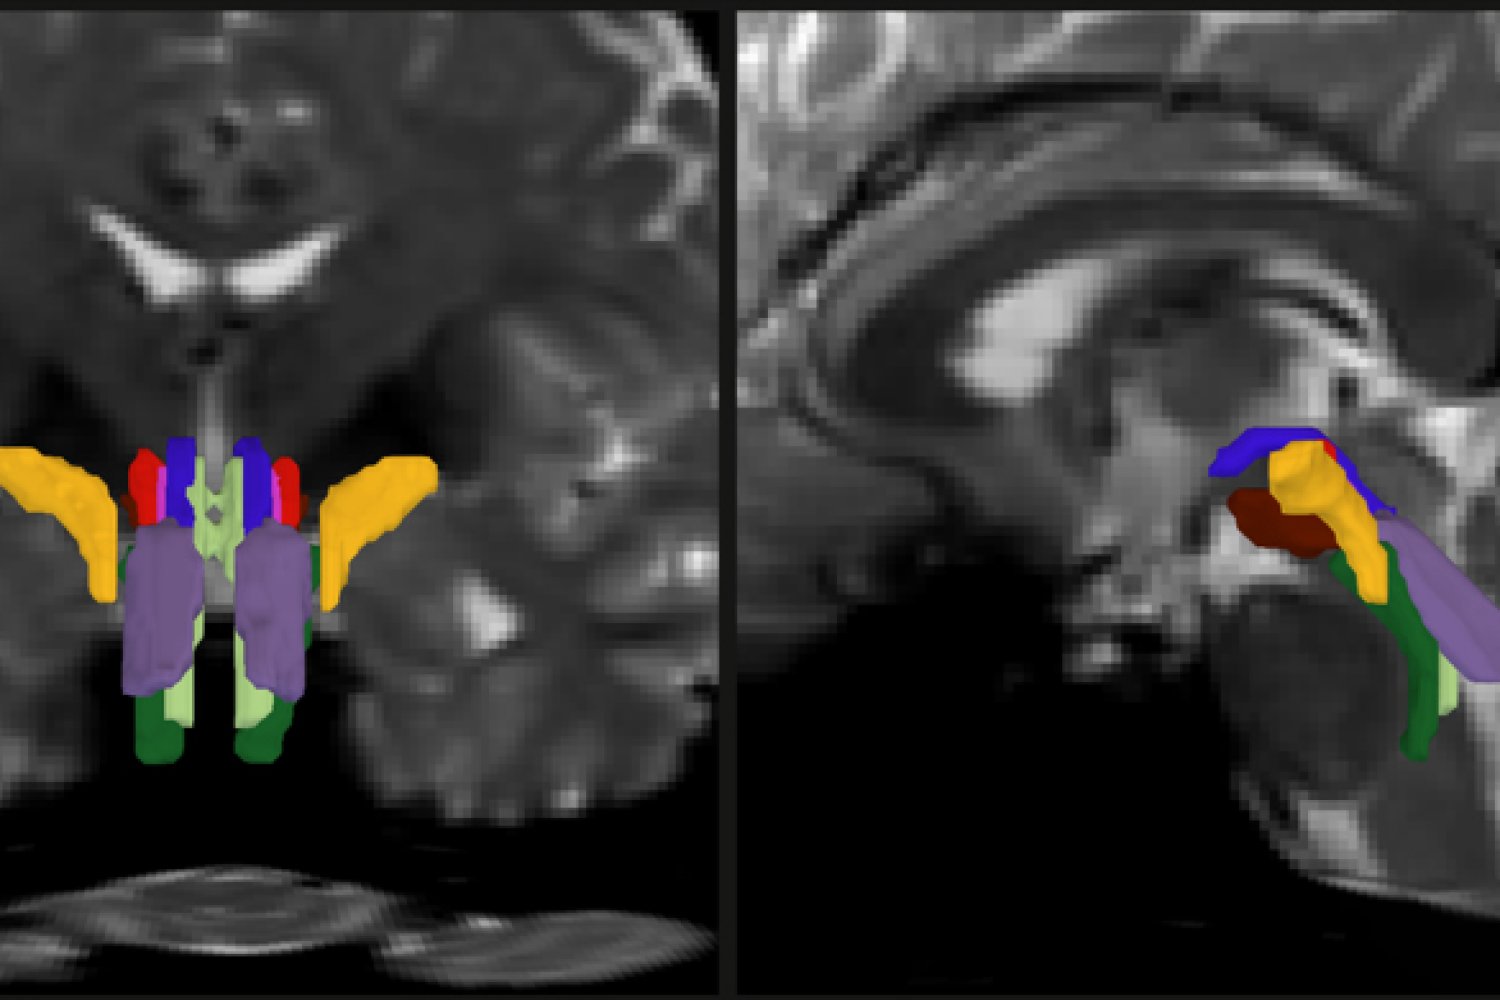

In two panels there are face-on and side-view cross sections of a human brain in pixellated gray. In the bottom center of each image color-coded crescent shapes delineate discrete nerve fiber bundles.

Researchers have developed a new way to resolve distinct bundles of nerve fibers in the brainstem. In this detail of a figure from the paper offering two different cross-section views of a human brain, individual bundles are segmented and color-coded.

Image: Mark Olchanyi/Emery Brown Lab